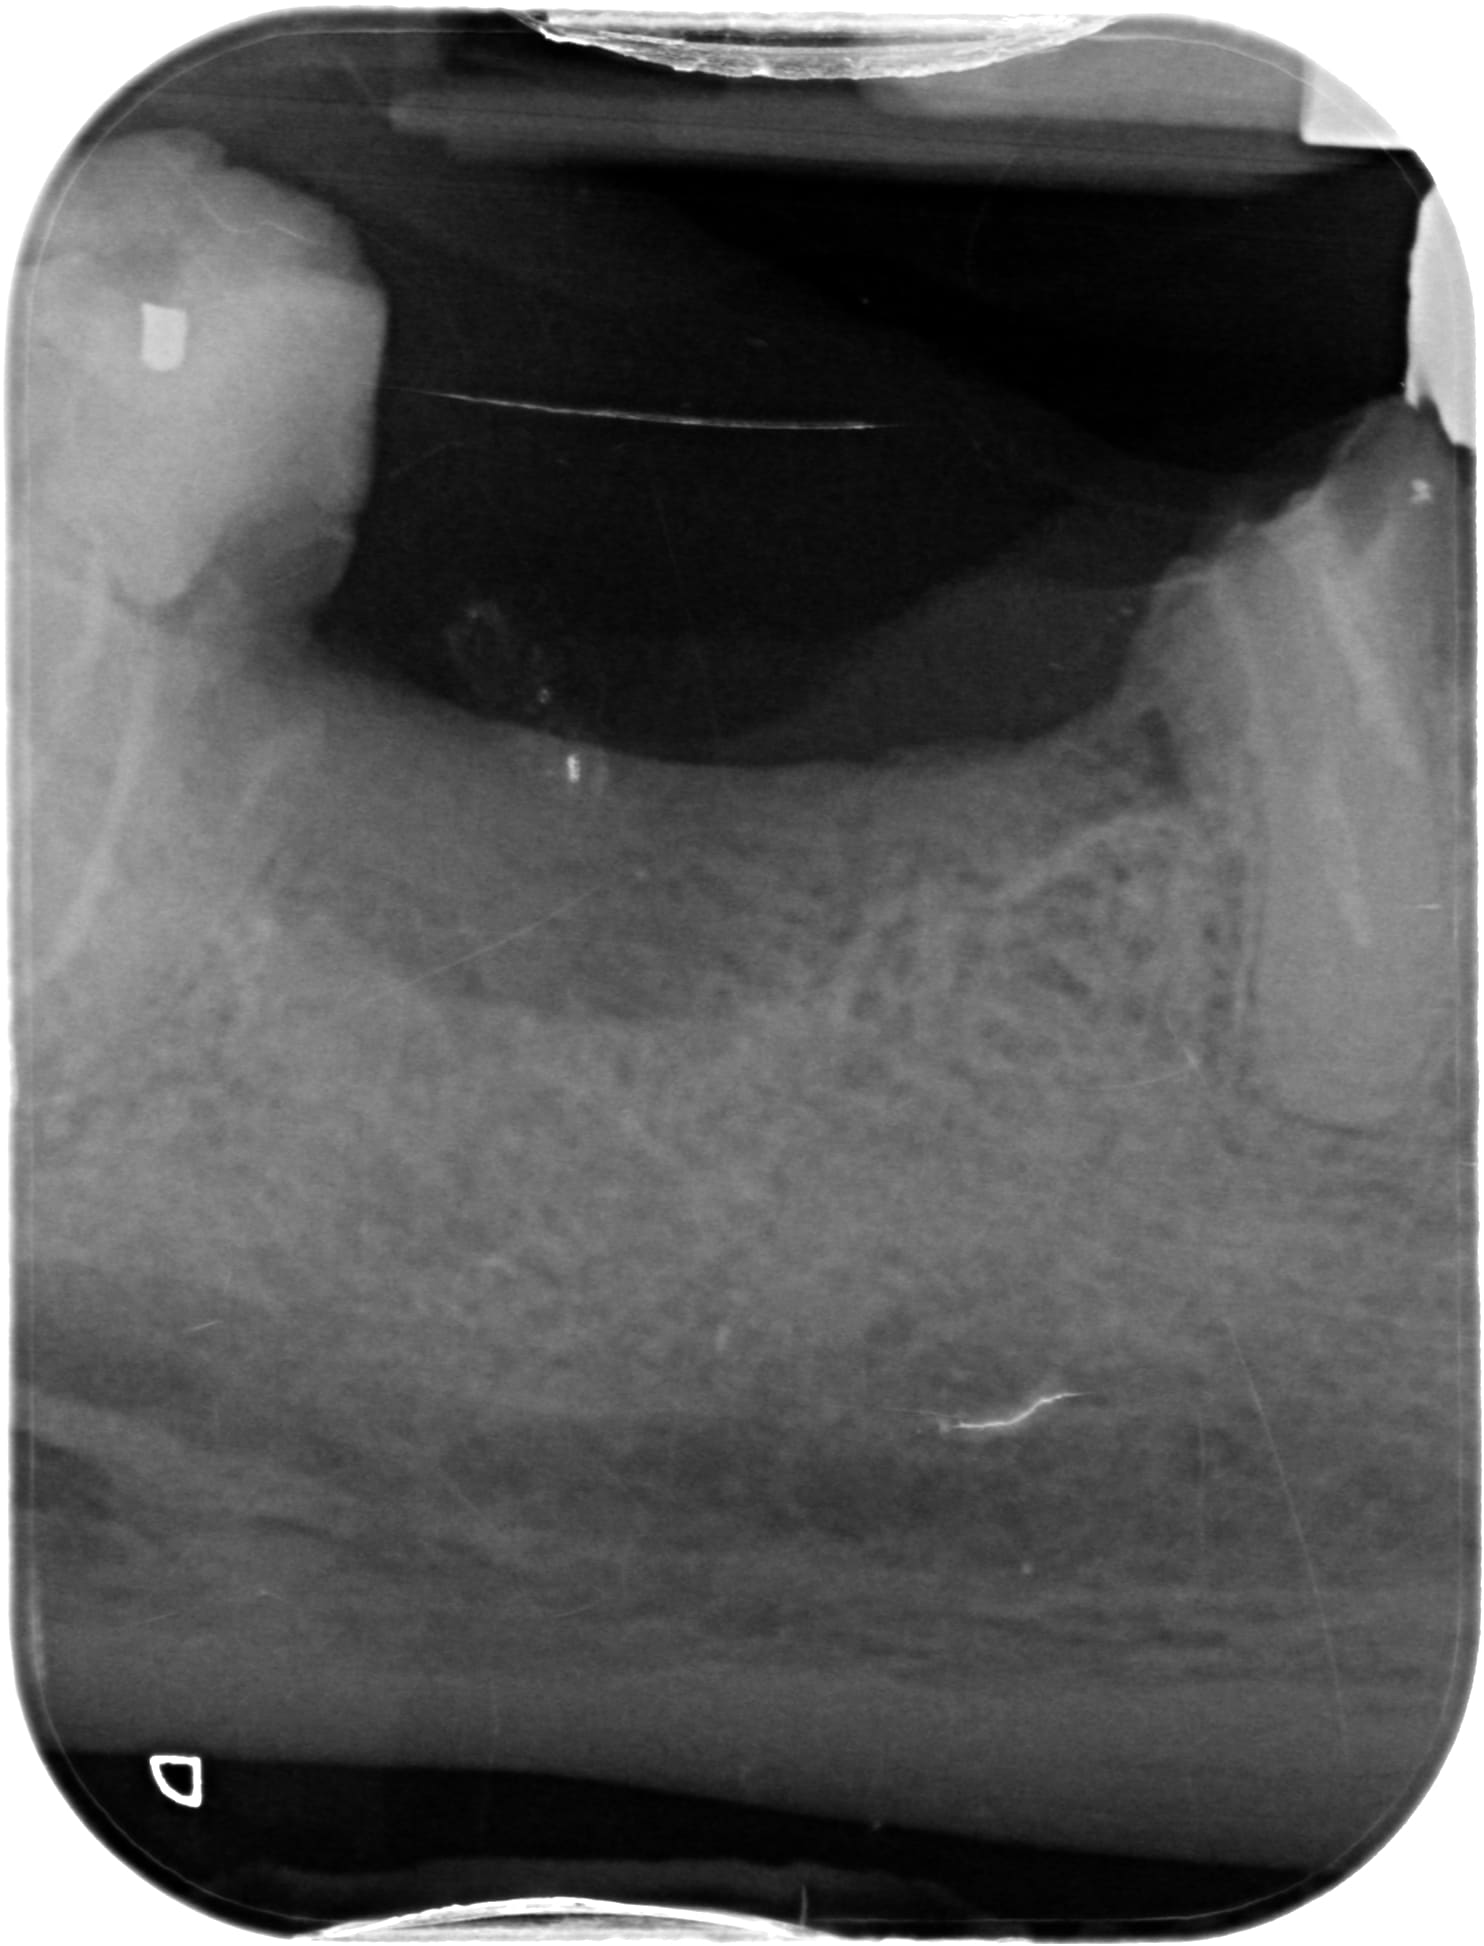

Pour les radios, vous avez donc la pano / 48 mes - racines mes de 46 / 44, 45, 46 mes

Je crois voir une image suspecte à l'apex de 14/15?